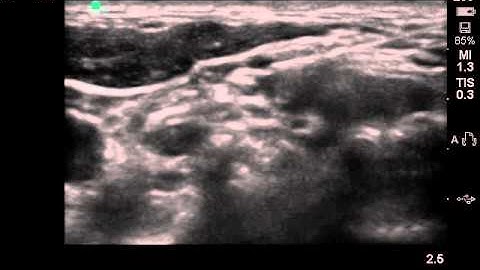

Intermediate Cervical Plexus Block